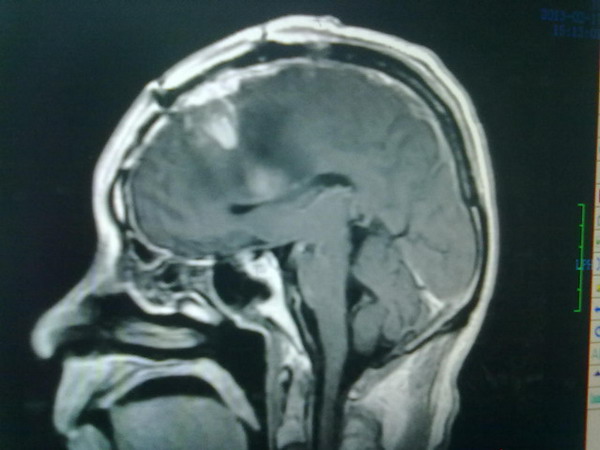

2013年2月5日上午8时,患者缓缓推进了手术室,麻醉、定位、消毒等各项手术步骤有序展开,10时手术正式开始,打开颅骨后,发现硬脑膜大片受肿瘤侵犯,而且跟矢状窦粘连紧密,脑压高,手术难度较大。手术医师沉着冷静,操作熟练,小心轻柔地沿着矢状窦侧分离肿瘤蒂部,阻断各条肿瘤供血动脉,分块切除肿瘤,经过近两个小时的精细操作,完整地全部切除肿瘤,并确保了矢状窦完好无损,脑副损伤降到最低限度,手术岀血少,量约300ml,不仅有利于患者术后康复,避免复发,也大大减少住院费用,减轻患者经济负担。

患者经过术后2周恢复,右侧肢体肌力恢复正常,无错乱言语,记忆力及定向力恢复正常,伤口愈合好并拆线,计划近日转骨科治疗骨折。

术后复查